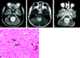

Cerebellar astrocytoma

A pilocytic astrocytoma (and its variant juvenile pilomyxoid astrocytoma) is a brain tumor that occurs more often in children and young adults (in the first 20 years of life). They usually arise in the cerebellum, near the brainstem, in the hypothalamic region, or the optic chiasm, but they may occur in any area where astrocytes are present, including the cerebral hemispheres and the spinal cord. [Source: Wikipedia ]